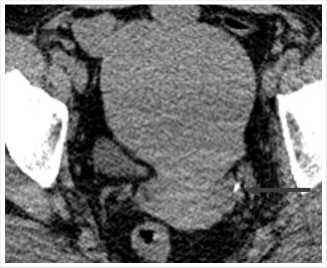

Рис. 2. МСКТ в нативном режиме, сделанная в марте 2023 г. Стрелкой указаны конкременты нижней группы чашечек правой почки.

10,9 ммоль/л, креатинин 124 мкмоль/л, мочевая кислота 445 мкмоль/л, пациентке рекомендовано выполнение анализа суточной мочи и низкодозная КТ органов мочевыделительной системы в нативном режиме. Диагностирована выраженная гиперурикурия до 870 мг, по данным КТ выявлено: Чашечно-лоханочная система (ЧЛС) справа расширена: чашечки до 17 мм, лоханка до 44 x 16 мм, в нижней группе чашечек правой почки определяются три конкремента, размерами до 4 мм, плотностью до 420 HU, в лоханке правой почки определяется крупный конкремент, размерами до 15 x 9,5 мм плотностью до 550 HU, мочеточник справа при нативном исследовании без значимого расширения, конкрементов в нем достоверно определяется. Вместе с тем, отмечается уплотнение клетчатки на уровне ЛМС справа, а также по ходу верхней трети мочеточника, где визуализируются лимфатические узлы, расположенные парааортально, максимальными размерами до 19 x 7 мм. ЧАС левой почки не расширена. Однако, отмечается наличие мелкого конкремента в области лоханочно-мочеточникового перехода, размерами до 4,8 x 3,5 мм, плотностью до 351 HU (Рис. 1, 2). Предложена госпитализация для проведения оперативного вмешательства по срочным показаниям с целью дренирования правой почки, от чего пациентка отказалась. Учитывая данные суточного анализа мочи, наличие конкрементов верхних мочевых путей (ВМП) относительно низкой плотности, заподозрен мочекислый (уратный) нефролитиаз. От проведения литолитической терапии в амбулаторных условиях пациентка также отказалась.